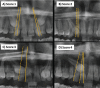

Material and methods: This retrospective study included an investigation of panoramic radiographs for patients attended College of Dentistry, Jazan University, Saudi Arabia. The incidence of canine impaction and orthodontic treatment difficulty index of maxillary canine impaction was assessed based on; (1) patient age, (2) vertical position, (3) buccolingual position, (4) horizontal position, (5) incisors alignment, (6) canine space, (7) midline coincidence, (8) rotation of impacted tooth. Statistical analyses were calculated by independent Chi-Square test. A P value of less than 0.05 was considered significant.

Results: Canine impaction was found in (1.9%) of the population. Bilateral canine impaction was present in 22.3% of the patient with impacted canines. Ninety two percent had impacted maxillary canines only while 7.5% had impacted maxillary canines with other impacted teeth. The ratio of maxillary to mandibular impaction was about 10:1. Females (69.4%) had more impacted canines than males (30.6%) with no significant sex predilection. Orthodontic treatment difficulty index was statistically significant (P ≤0.05) in males more than females. Males revealed statistically significant (P ≤0.05) difficulty regarding canine angulation and the vertical position while females showed significant difficulty regarding dental midline and incisors irregularity or crowding of incisor segment.